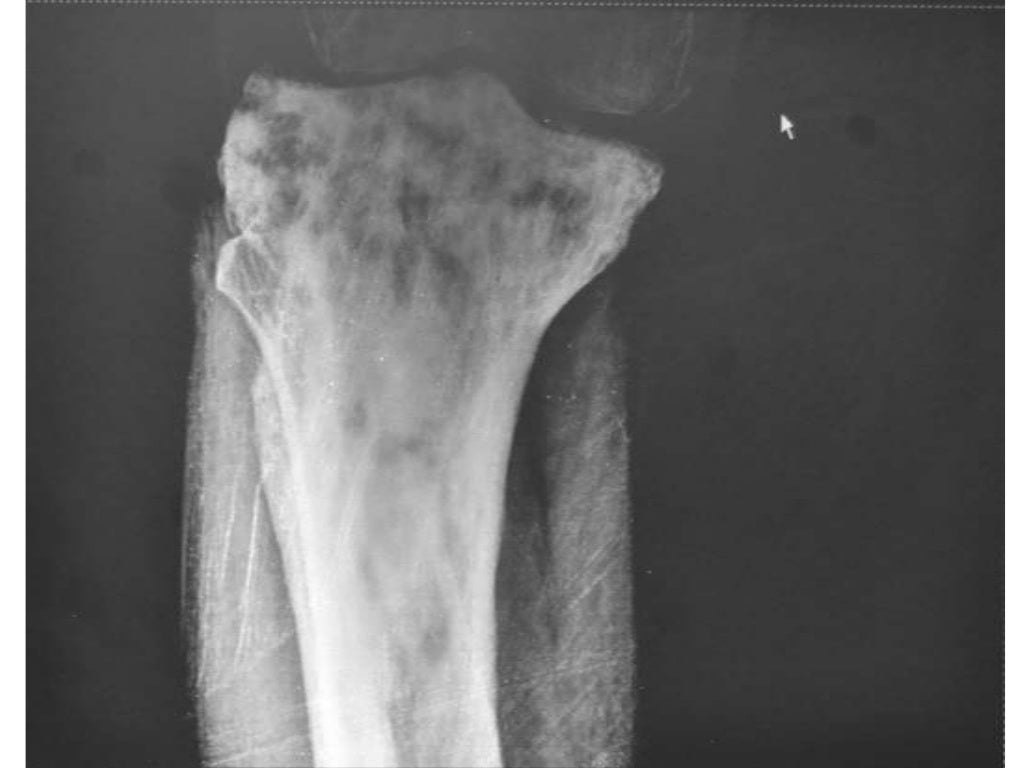

XRay showing Paget's disease of the tibia bone Stock Photo Alamy Can Paget's Disease Of The Bone Kill You Paget's disease is treated with medicines called bisphosphonates. Paget's disease is a chronic condition that affects the skeleton and causes abnormal bone remodeling. Paget's disease can cause a dull pain in your bones at night or when you're resting. Paget’s disease is a chronic disorder that affects the bones and causes them to grow larger and weaker than normal. Find. Can Paget's Disease Of The Bone Kill You.